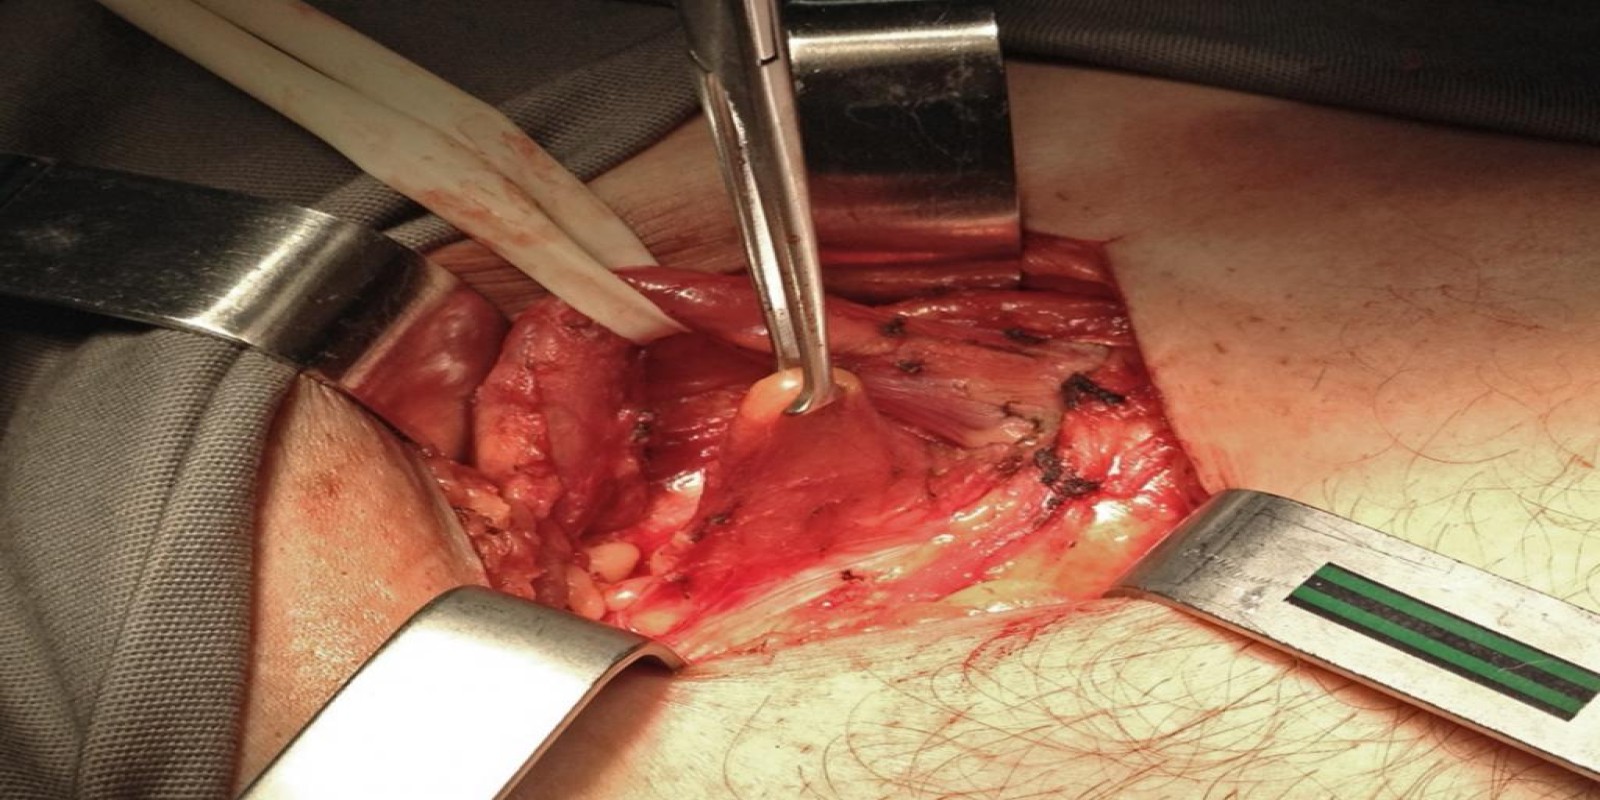

Caso Código 103B de Hérnia Inguinal

Cod.: 103B